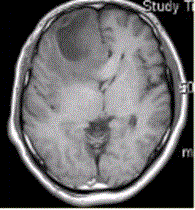

问题 患者女,67岁,头痛伴呕吐1周。既往体健。MR表现如下图。 多形性成胶质细胞瘤的转移途径不包括

选项 A.室管膜 B.淋巴转移 C.脑膜 D.血管周围间隙 E.也可转移至颅外

答案 B